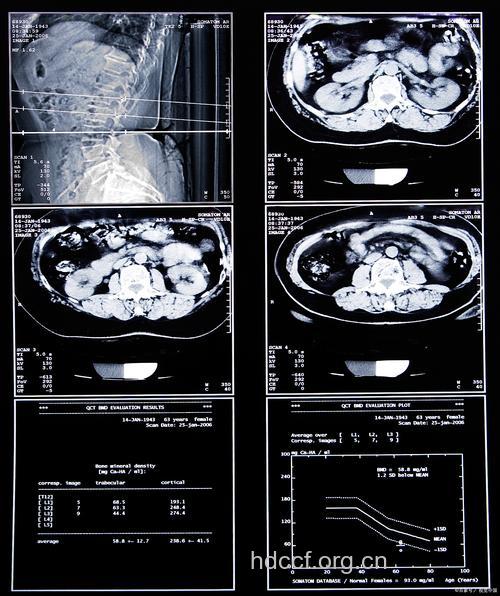

11、CT检查有三种方法,一是平扫,为普通扫描,是常规检查;二是增强扫描,从静脉注入水溶性有机碘,再进行扫描,可以使某些病变显示更清楚;三是造影扫描,先行器官或结构的造影,再行扫描,如向脑池内注入造影剂或空气进行脑池造影,再扫描,可清楚显示脑池及其中的小肿瘤。

12、CT对所有器质性疾病都可以进行检查,尤其对密度差异大的器质性占位病变都能检查出来并做出定性诊断。但最适于CT检查的病是脑部疾病,其中对肿瘤、出血及梗塞等病检查效果最好,其次是腹部实质脏器的占位病变,如肝、脾、胰、肾、前列腺等部位的肿瘤,对乳腺、甲状腺等部位的肿块也能显示并做出诊断;再其次则是对胸腔、肺、心腔内的肿块,脊柱、脊髓、盆腔、胆囊、子宫等部位的肿块检查。CT对一些弥漫性炎症及变性性病变的检查效果稍差,如对肝炎,CT检查无多大价值,对胃肠道内病变的检查,CT不如内窥镜。